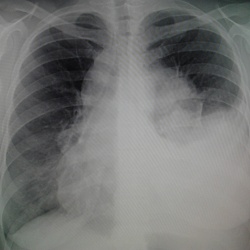

Поделитесь пожалуйста своим мнением! Мужчина 75лет, поступает в приемный покой с температурой 39; повышение АД; ИБС; ХСН; склеры желтые. В н/ отделе справа дыхание не проводится. Просят исключить...